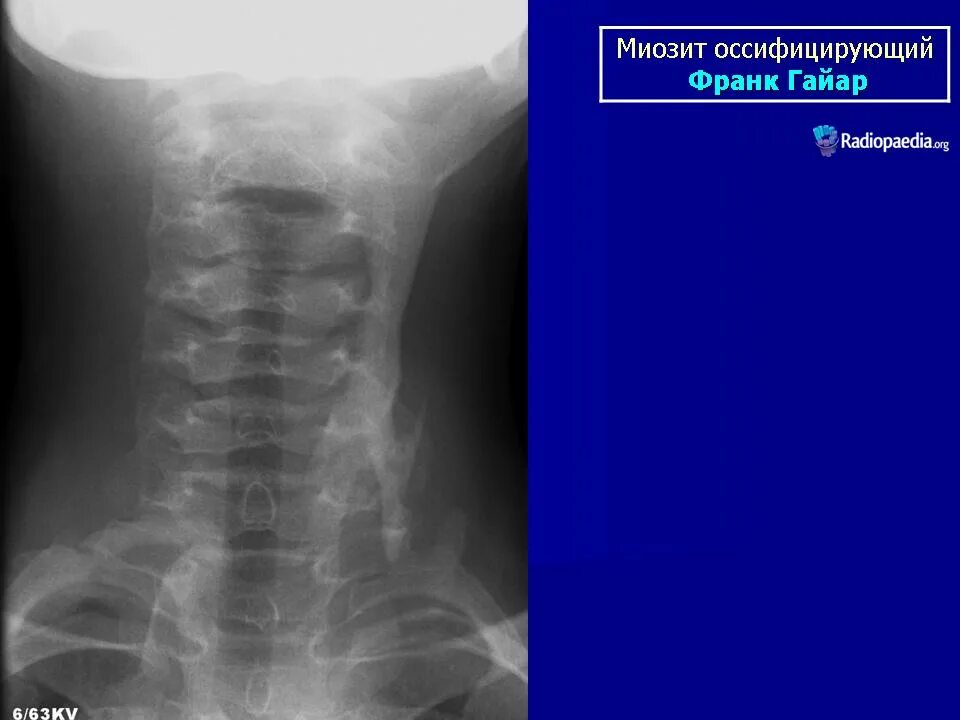

Оссифицированный миозит